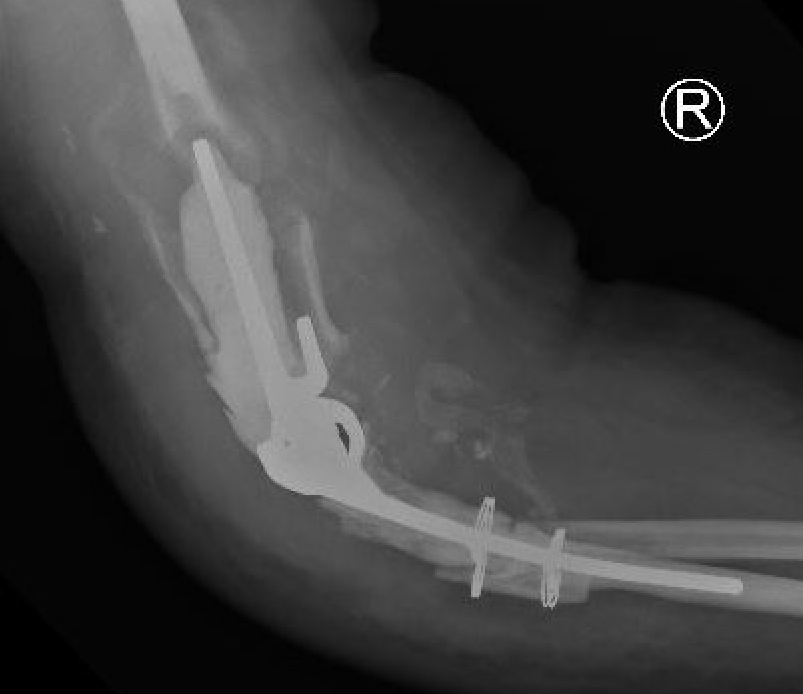

Intraoperative fracture

Humeral condyles

Ulna at risk

- slight bend / small diameter / relatively thin cortical bone

- perforations can allow cement extrusion

Aseptic Loosening

- systematic review of 3000 TEA

- loosening rates 10% for unlinked and 14% for linked prosthesis

Periprosthetic Fracture